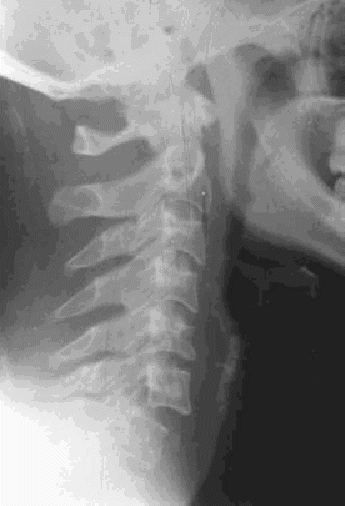

| Figura 16.Radiografía lateral de cuello: Luxación C6-C7 con anterolistesis de C6, desalineación de las líneas radiológicas (fig. 14) con compromiso del canal raquídeo, sig-no de la faceta desnuda y pseudoagujero de conjunción. Obsérvese la enorme importan-cia de visualizar el raquis cervical inferior en esta proyección. También puede verse una discreta anterolistesis de C3 sobre C4 con leve desalineación de las líneas de los cuerpos vertebrales anterior y posterior. |